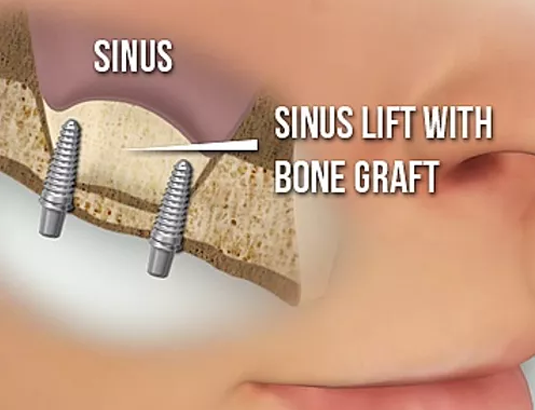

Bone Graft & Sinus Lift

When a tooth has been missing for a long time or in case of infections or periodontal disease